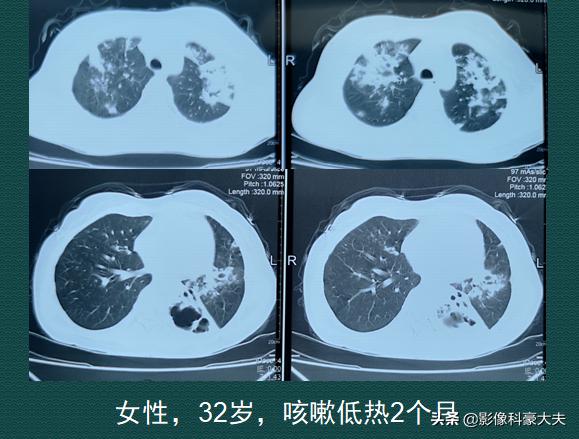

年轻的宝妈,肺里烂出大空洞

一位32岁的女士,反复咳嗽两个月,经常在下午发低烧,晚上睡觉时出汗特别多(夜间盗汗),胃口也很差,最近今天开始吐血块,还有些暗红色的东西。呼吸科医生听诊肺里很多啰音,建议她马上CT检查:

情况很不妙,人体有5个肺叶子,她的3片肺叶都有大量白色斑片状炎症,像乌云密布,属于重症肺炎了;还不止这些,她的左下肺叶烂出一个黑色不规则的大空洞,她最近吐的暗红色物,就是坏死的肺组织。这是典型的肺结核,干酪样肺炎伴空洞形成,重症了。